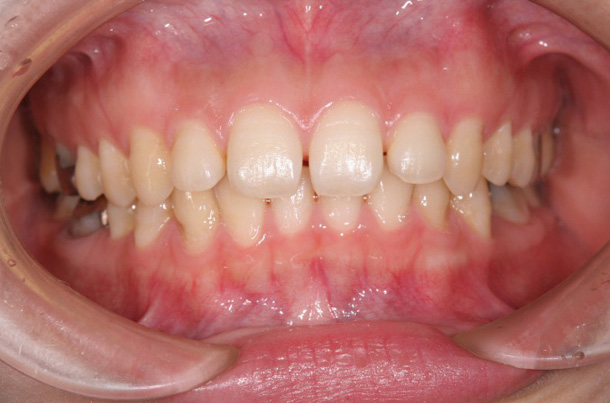

症例1:叢生

主訴:歯並びを治したい

年齢:20歳

診断:上下顎叢生・上顎骨幅径の狭小

装置:上顎急速拡大装置・上下顎ブラケット装置

治療期間:2年5ヶ月(来院回数29回)

抜歯:左右上下顎小臼歯の4本

費用:750,000円+税

矯正前

矯正後